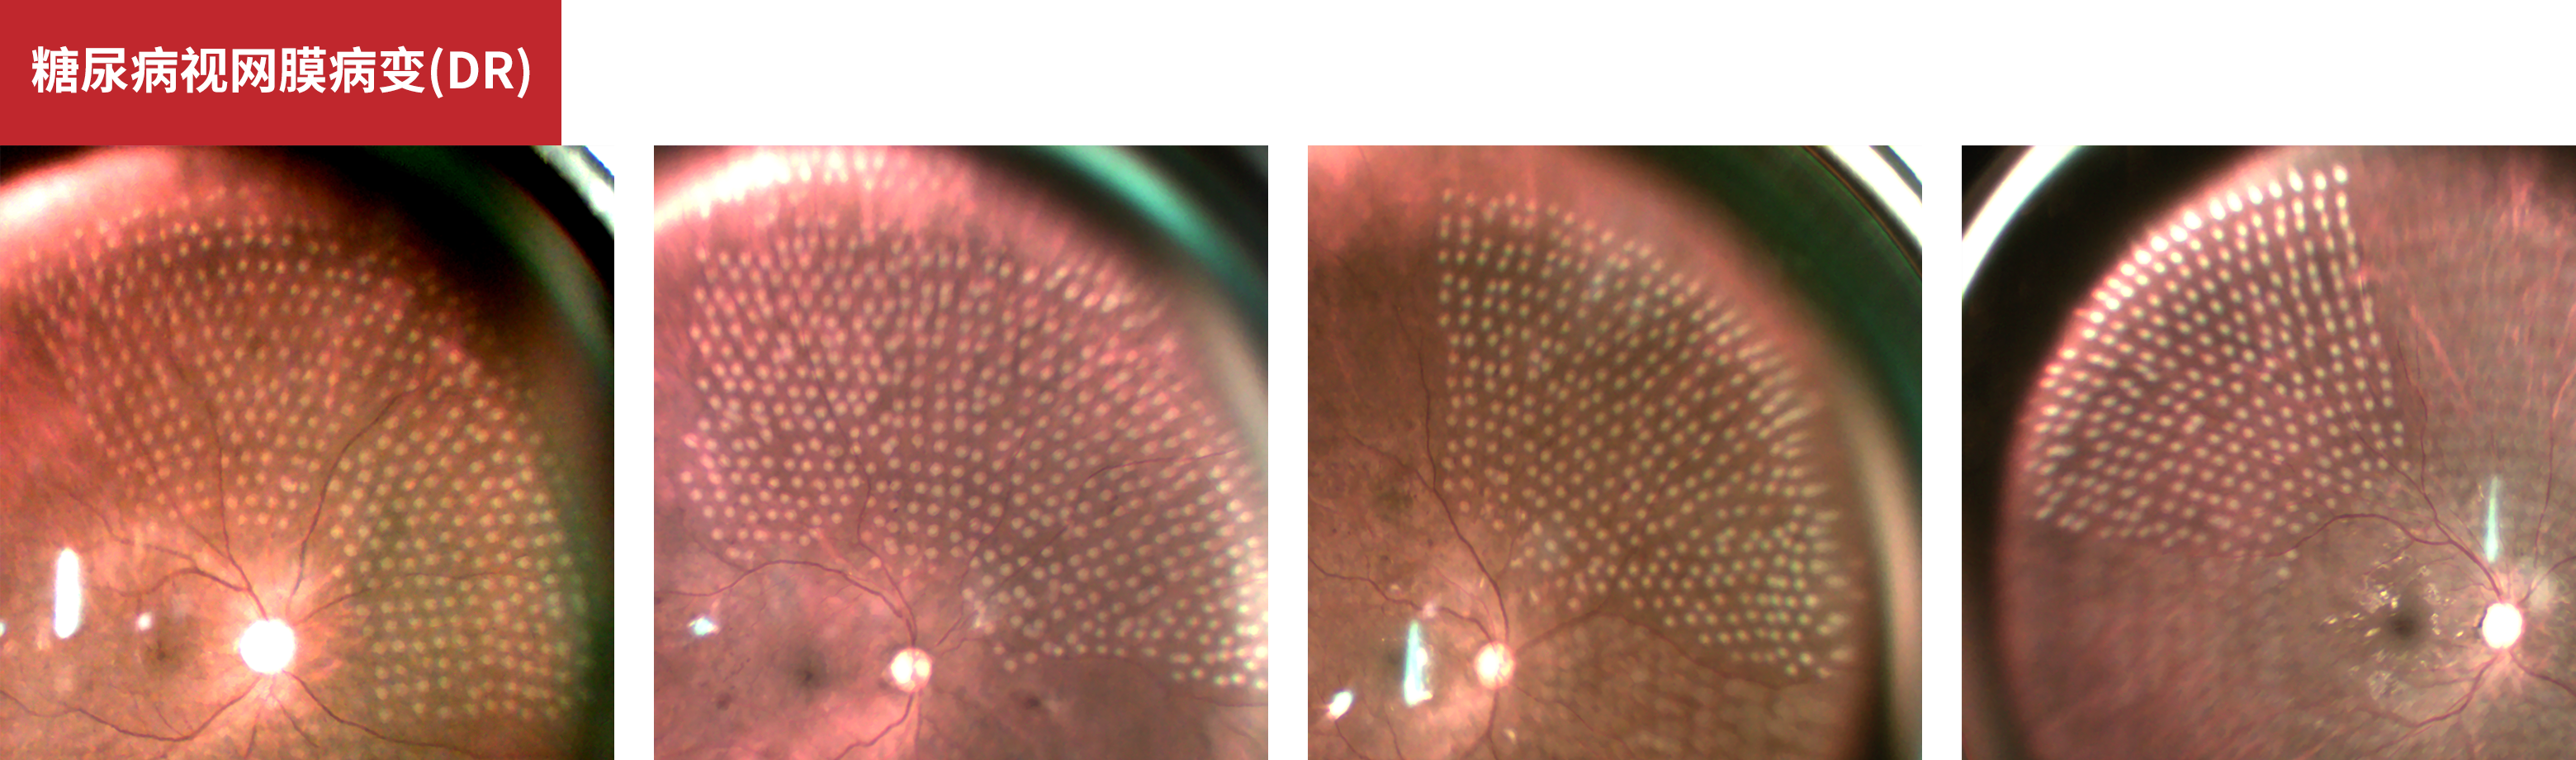

糖尿病视网膜病变(DR)

Pan Retinal Photocoagulation

鸣谢:山东省第一医科大学附属眼科医院孙晓蕾教授